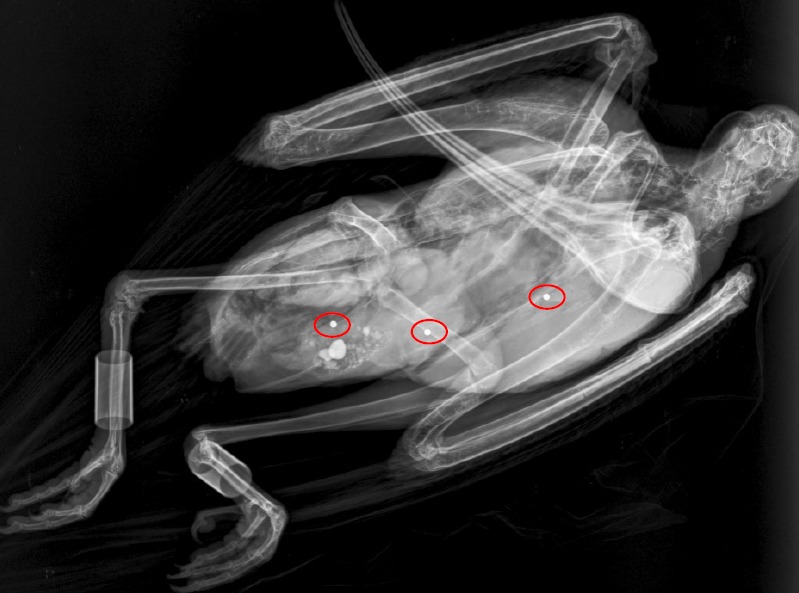

L’urgenza di questo messaggio è resa evidente dai recenti fatti avvenuti in Italia. A una settimana dalla chiusura della stagione venatoria, un giovane Ibis eremita non inanellato è stato trovato gravemente ferito da colpi di fucile in Abruzzo, in provincia di Pescara.

Nonostante le misure preventive, l’animale è stato colpito in una zona di caccia nei pressi di Penne. Ha subito un intervento chirurgico d’urgenza e resta incerto se potrà mai tornare a volare.